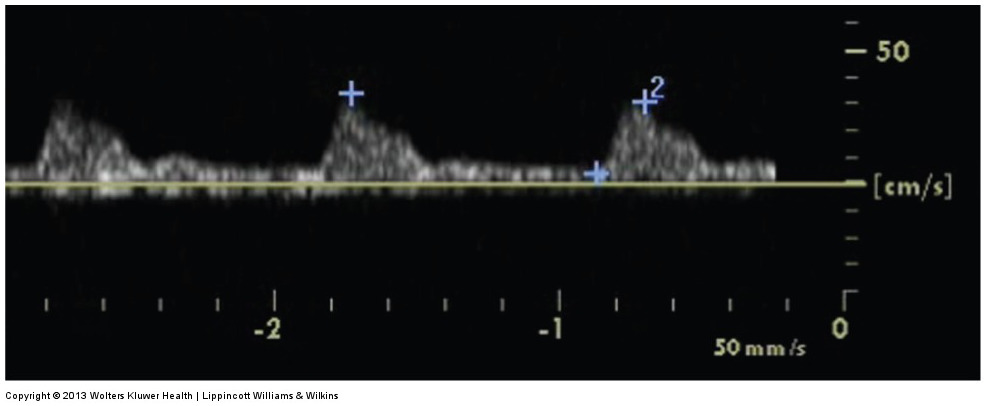

a doppler waveform taken proximal to a stenosis

what does image A represent

a doppler waveform taken at the area of maximum velocity shift within a stenosis

what does image B represent